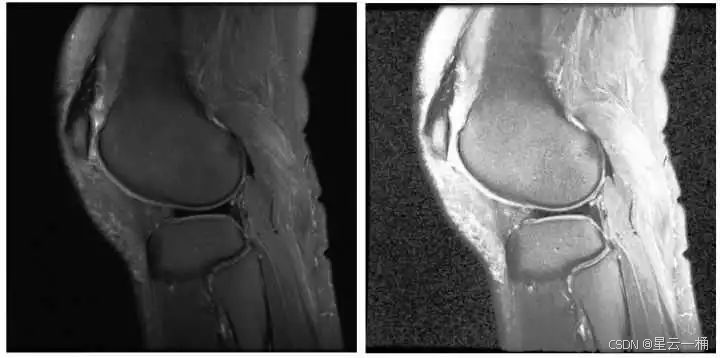

下面是一个例子,发现经过HE之后的图片出现了大量噪点:

% 读取图像

img = imread('pout.tif');

imshowpair(img, enhancedImg, 'montage');

title('原图 (左) vs CLAHE增强后 (右)');